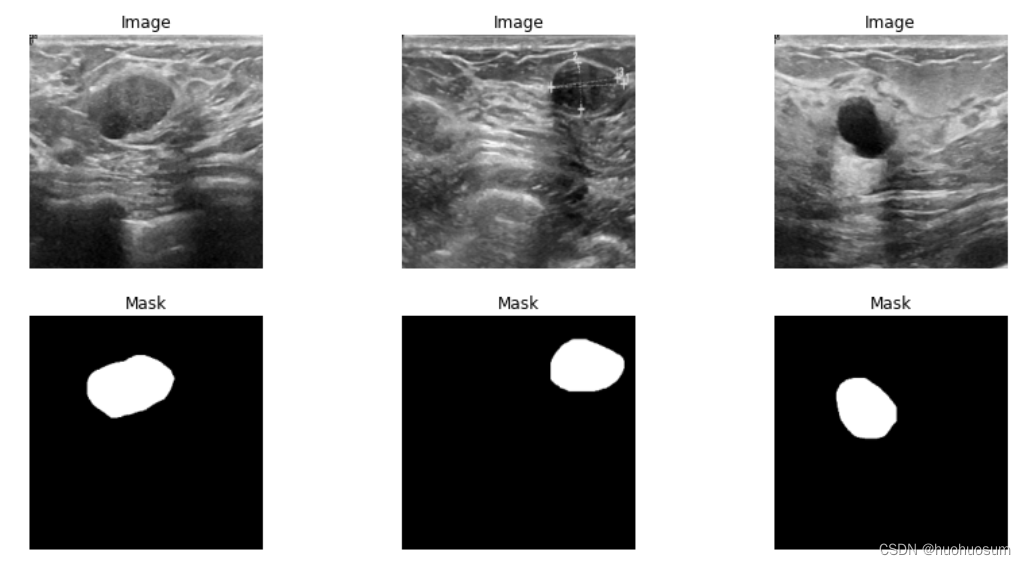

(Breast Ultrasound Image)是一个包含乳腺超声图像的分类和分割数据集。该数据集包括了 2018 年收集的乳腺超声波图像,涵盖了 25 至 75 岁的 600 名女性患者。数据集由 780 张图像组成,每张图像的平均大小为 500*500 像素。这些图像被划分为三类:正常、良性和恶性。而在良性和恶性乳腺超声图像中,还包含了对应胸部肿瘤的详细分割标注,为深入研究和精准诊断提供了关键信息。这份数据集为乳腺癌研究提供了丰富的图像资源和宝贵支持。

通过对比MedNIST数据集和BUSI数据集的不同,可以发现BUSI数据集的图像有以下特点:

(1)BUSI数据集图像尺寸大小不一致;

(2)BUSI数据集图像通道数量为3;

(3)BUSI数据集每类目录下,除了原始图像数据外还包括掩模数据。